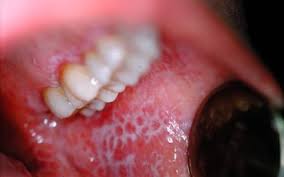

Le lichen plan buccal siège: sur la face interne des joues (face postérieure, sous forme de ponctuations blanches, isolées, ou de réseaux et d’arborisations brillantes), sur le dos de la langue (stries blanchâtres, plaques ou arborisations, ou nappes ou traînées opalescentes), sur le bord libre des lèvres (fines arborisations brillantes) et encore sur le palais, sur la gencive (notamment derrière les dents de sagesse).

La forme scléreuse hypertrophique, siégeant le plus souvent à la face postérieure de la joue, autour de la dent de sagesse inférieure. Les lésions s’étendent en nappes, d’épaisseur irrégulière, parfois mamelonnées, ou végétantes.